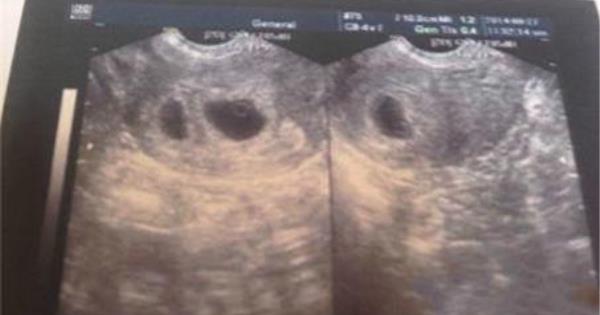

30歲的蔣蔣懷孕10周時到醫院產檢,醫生告訴她,可能是雙胞胎。半個月後去複查,檢查結果為“雙胎囊雙原始心管搏動”,是雙卵雙胎。 這可把蔣蔣樂壞了。雖然早知道家族裡有雙胞胎基因,但是真的確定的時候還是覺得很幸運。 然而,幸福太短暫,僅僅持續了一個月。  一個月後,當蔣蔣再去產檢時,醫生對照此前的B超圖像發現,兩個寶寶居然是在一個胎囊裡,情況不太好,故建議她重新檢查。而重照B超的結果讓林女士嚇了一跳:只有一個胎兒,另一個“不翼而飛”了。 B超檢查沒問題,也沒有流產跡象,寶寶到底去哪兒了? 醫生表示,蔣蔣的這種情況在臨床中並不罕見,和自然流產一樣,是胎兒在宮內停止發育所致。

為什麼好好的雙胞胎會停止發育?這倒是可以用達爾文的《進化論》來解釋。  原來,早期妊娠是雙胞胎,但在發育過程中,其中一個沒有正常發育,兩個胚胎互相競爭,優勝劣汰,較弱的胚胎競爭不過較強的那個,自然也就夭亡了。而由於不斷受到另一正常妊娠胎兒羊膜囊擠壓,死胎部分組織被吸收,剩下的胎兒仍可正常發育。待到產婦分娩時,夭亡的胎兒就變得又扁又薄,像紙一樣,但輪廓仍清晰可辨。在檢查手段不發達的年代,有的產婦甚至到分娩時都沒有發現自己懷的是雙胞胎。

為何會有這樣的優勝劣汰的情況發生?  醫生表示,雙胎變單胎的原因很可能和雙胎輸血綜合征有關。 一般來說,兩個胎兒共處一室時,通常會相安無事,但若是出現血管吻合異常,即一個胎兒的動脈和另一個胎兒的靜脈不小心搭在一起,一個胎兒的血液就會源源不斷流向另一個胎兒體內。

此時,輸血方胎兒只是一個“過渡”,會慢慢變小。若發生在孕早期,其中一個胎兒死亡,分娩時就會形成紙樣胎兒或僅僅是部分組織塊。 唉,真是“本是同根生,相煎何太急”啊。不過也要提醒孕婦們,如果孕早期發現懷上雙胞胎,最好等到11-13周B超確認後再高興也不遲。當然,即便是確診,定期的體檢也是必不可少的,一旦發現異常要及時處理。而如果胎兒“消失”發生在妊娠3個月後,那麼母體和胎兒出現併發症的風險會大增,產婦也應嚴密觀察。 臨床表現為羊水過多、雙胎靜脈吻合、紙樣胎兒、胎兒水腫等,可利用B超在產前作出診斷。治療方法主要有以下幾種: 1、胎兒鏡下選擇性激光電凝治療 在胎兒鏡下激光燒灼胎盤血管吻合支,以阻斷血流,理論上能從根本上治療此病,這是對各期都有效的方法,但需要專業的技術和足夠的器械。到目前為止,對於26周以前的TTTS,胎兒鏡下選擇性激光電凝胎盤的吻合血管是首選。激光電凝與連續性羊水減量相比,可以提高圍生期的生存率,降低神經係統的發病率。